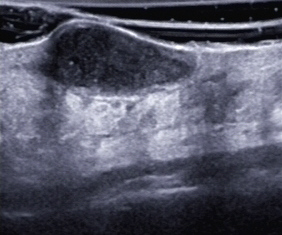

Eine erneute lokale sowie antibiotische Therapie führten zunächst zu einem Teilerfolg, jedoch wurde die Patientin bereits nach wenigen Wochen erneut vorstellig – es war wieder zu einer Abszedierung gekommen (sonografische Darstellung, s. Abb. 4–6)